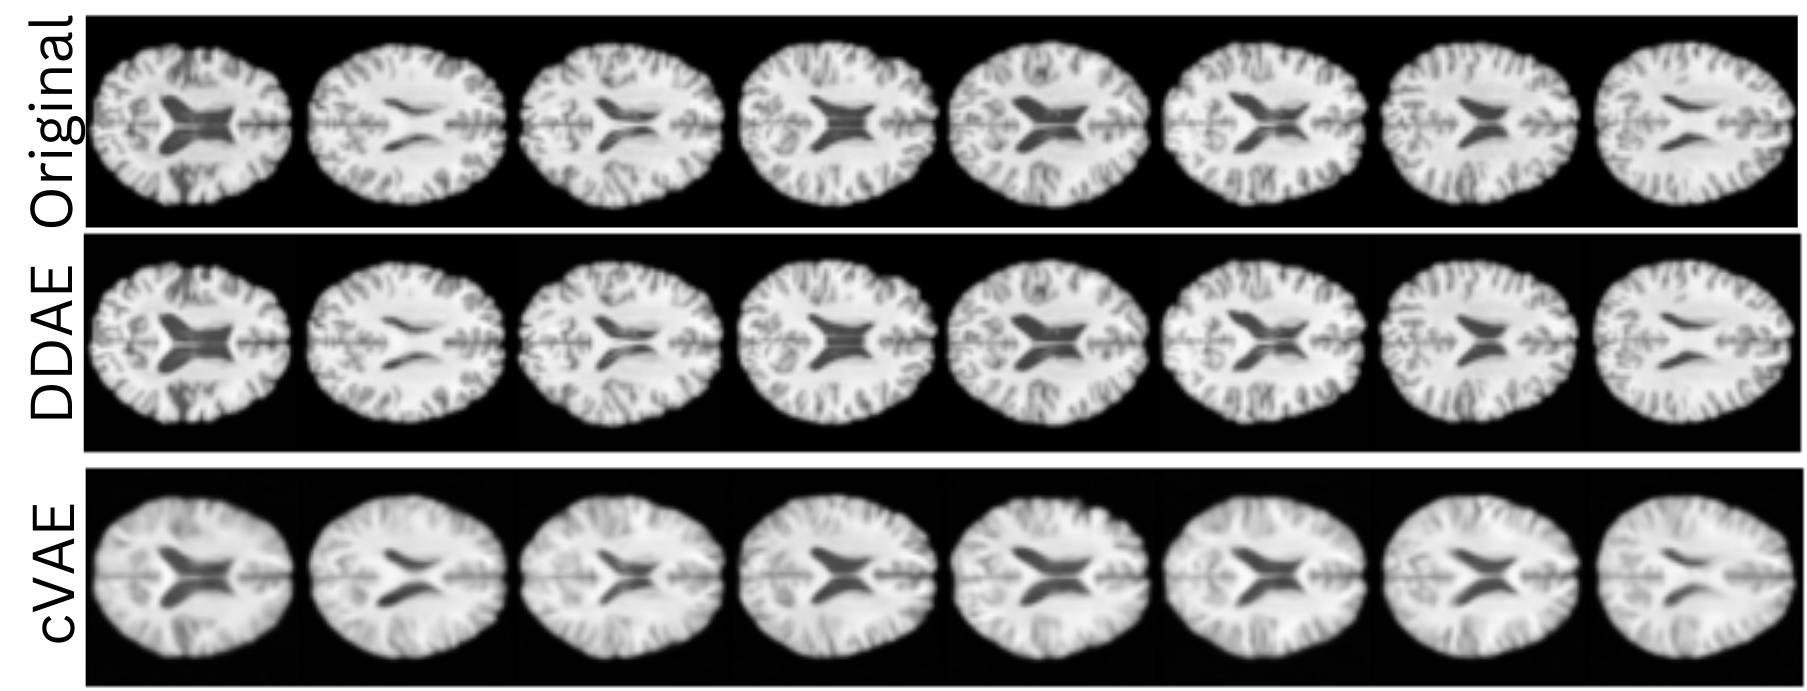

Figure 3: Example Reconstructions from our Disentengled diffusion autoencoder (DDAE) compared to a cVAE. The first row shows original images from our dataset, the second row shows reconstructions from our model and the third row shows reconstructions from a cVAE.

For cVAE and DDAE, we reconstructed the original image for each sample without modifying the site label. Figure 3 shows a selection of generated images for the cVAE and DDAE models, where we can see visually that the DDAE gives better results with the cVAE model producing blurry images. To quantitatively evaluate the quality of the generated images and the ability of the proposed method to preserve the integrity of the image, we calculated the fretchet-inception distance (FID) [14] score between the original and site adjusted generated images for each model (see Table 1). The DDAE model achieved the lowest FID score, further illustrating that our model can generate higher-quality images than previous approaches.